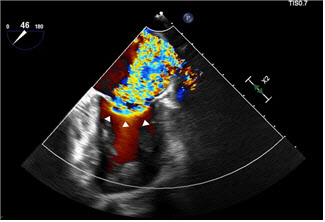

인천세종병원에 따르면 승모판막 부전 환자를 대상으로 허벅지 정맥에 미세도관(카테터)을 넣어 심장까지 접근해 승모판막의 전엽과 후엽을 클립으로 고정하는 마이트라클립 시술을 시행하고 있다. 카테터 끝에 장착된 클립 장치를 이용해 느슨하거나 제대로 닫히지 않는 승모판을 고정하면서 혈액 역류를 차단하는 방식이다. 모든 시술 과정은 심장초음파 및 X-ray 영상 장비로 실시간 관찰하며 진행된다.